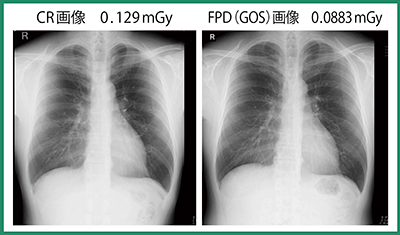

EIと,EITに対する撮影線量の偏差を表す数値であるDI(Deviation Index)を指標に,フォトタイマーを変更するなど撮影条件の補正を行いながら実際の臨床写真で画質評価を繰り返した。図4に,当院でのDI偏差による線量の指標を示す。画質評価の結果,0.0883mGyでの撮影が可能となり(図5), CRと比較して31.55%の線量低減率が達成できた。それでも画質はCRよりも向上しており(図6),視覚的には数値以上の効果を実感している。現在の撮影条件ではDIがマイナス側に偏差することが多く,目標よりも低い線量で撮影できていることから,将来的にはEITを230程度まで下げられるのではないかと考えている。

図6 CR画像と新撮影条件によるCALNEO Smart画像の比較

(CR比30%低減画像)